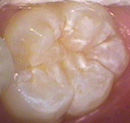

The most common area for children to get decay (like most adults) is on their permanent back teeth (molars). The molars have very deep grooves and pits on the chewing surfaces. This is where food and bacteria hide and form cavities. No matter how well your child brushes, it is nearly impossible to remove all of the bacteria from these grooves and pits.

Sealants are a white or tooth shaded material that is bonded to the chewing surfaces of the back teeth, sealing off deep grooves and pits. This makes the grooves of the teeth smoother so your toothbrush can more easily keep the tooth clean.

Before Sealant